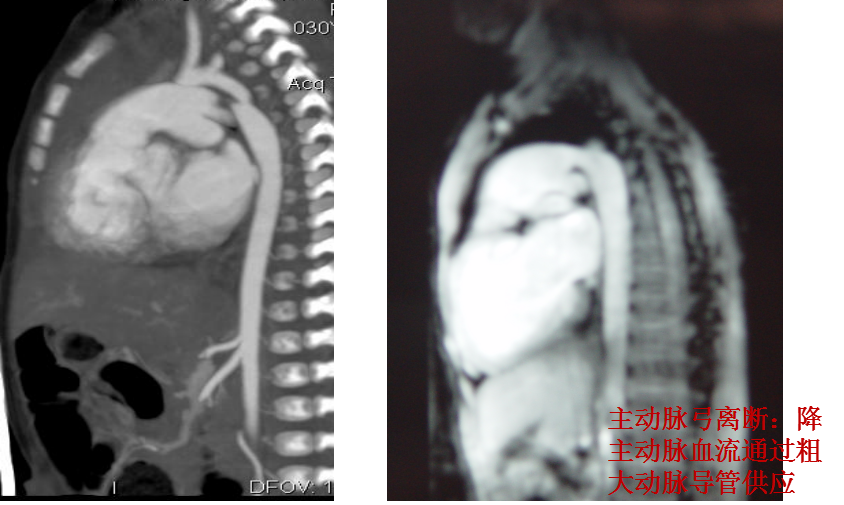

主动脉弓缩窄伴弓部及降部发育不良 主动脉弓离断:升主动脉与降主动脉不连续,

降主动脉通过粗大动脉导管供血

5、心脏核磁共振(Magnetic Resonance Imaging,MRI)

√ 心内畸形

√ 大血管形态

主动脉弓降部局限性缩窄